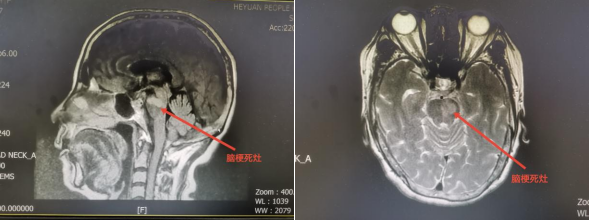

近期,六十多岁的张阿婆因“头晕1天,右侧肢体麻木、无力12小时”入院,患者表现为右侧肢体偏瘫无力,伴言语不清,头晕明显,翻身坐卧困难,站立行走不能,吞咽饮水呛咳,来我院急诊就诊,急诊完善颅脑CT及颅脑MRI检查,诊断:脑桥左侧急性脑梗死,遂收入我院神经内科住院,予药物对症处理。

颅脑MRI图像